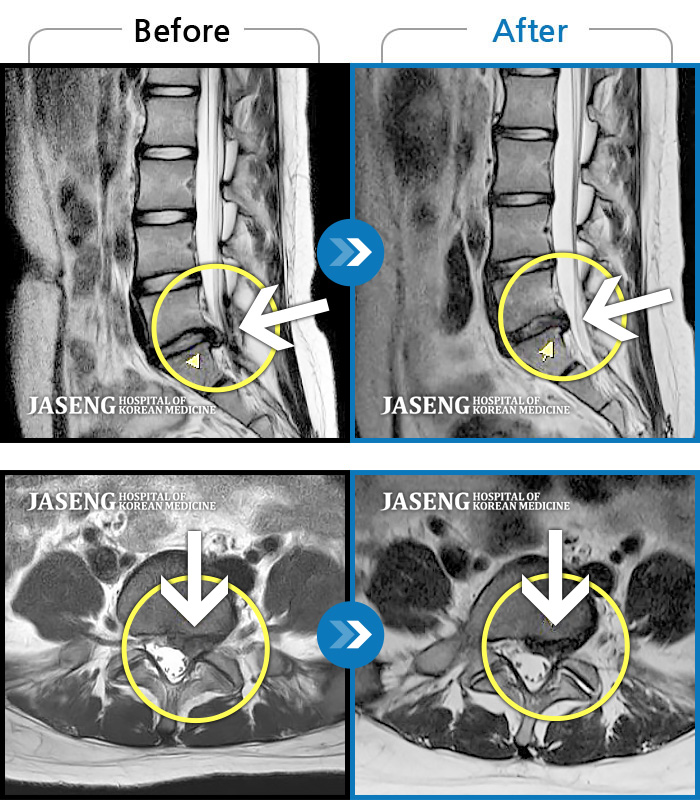

허리디스크

광주 · 김동은 원장

요추 5번과 천추 1번 사이에서 탈출된 디스크가 신경막을 압박

촬영시기

2017.08.26 ~ 2018.03.31

2020.01.23

조회수 5,097